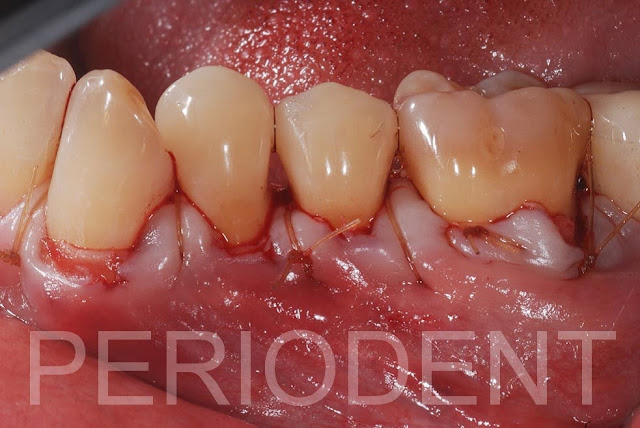

陳柏堅醫師發表左下多顆牙齦退縮,採用Tunneling + Connective Tissue Graft作牙根覆蓋

手術前